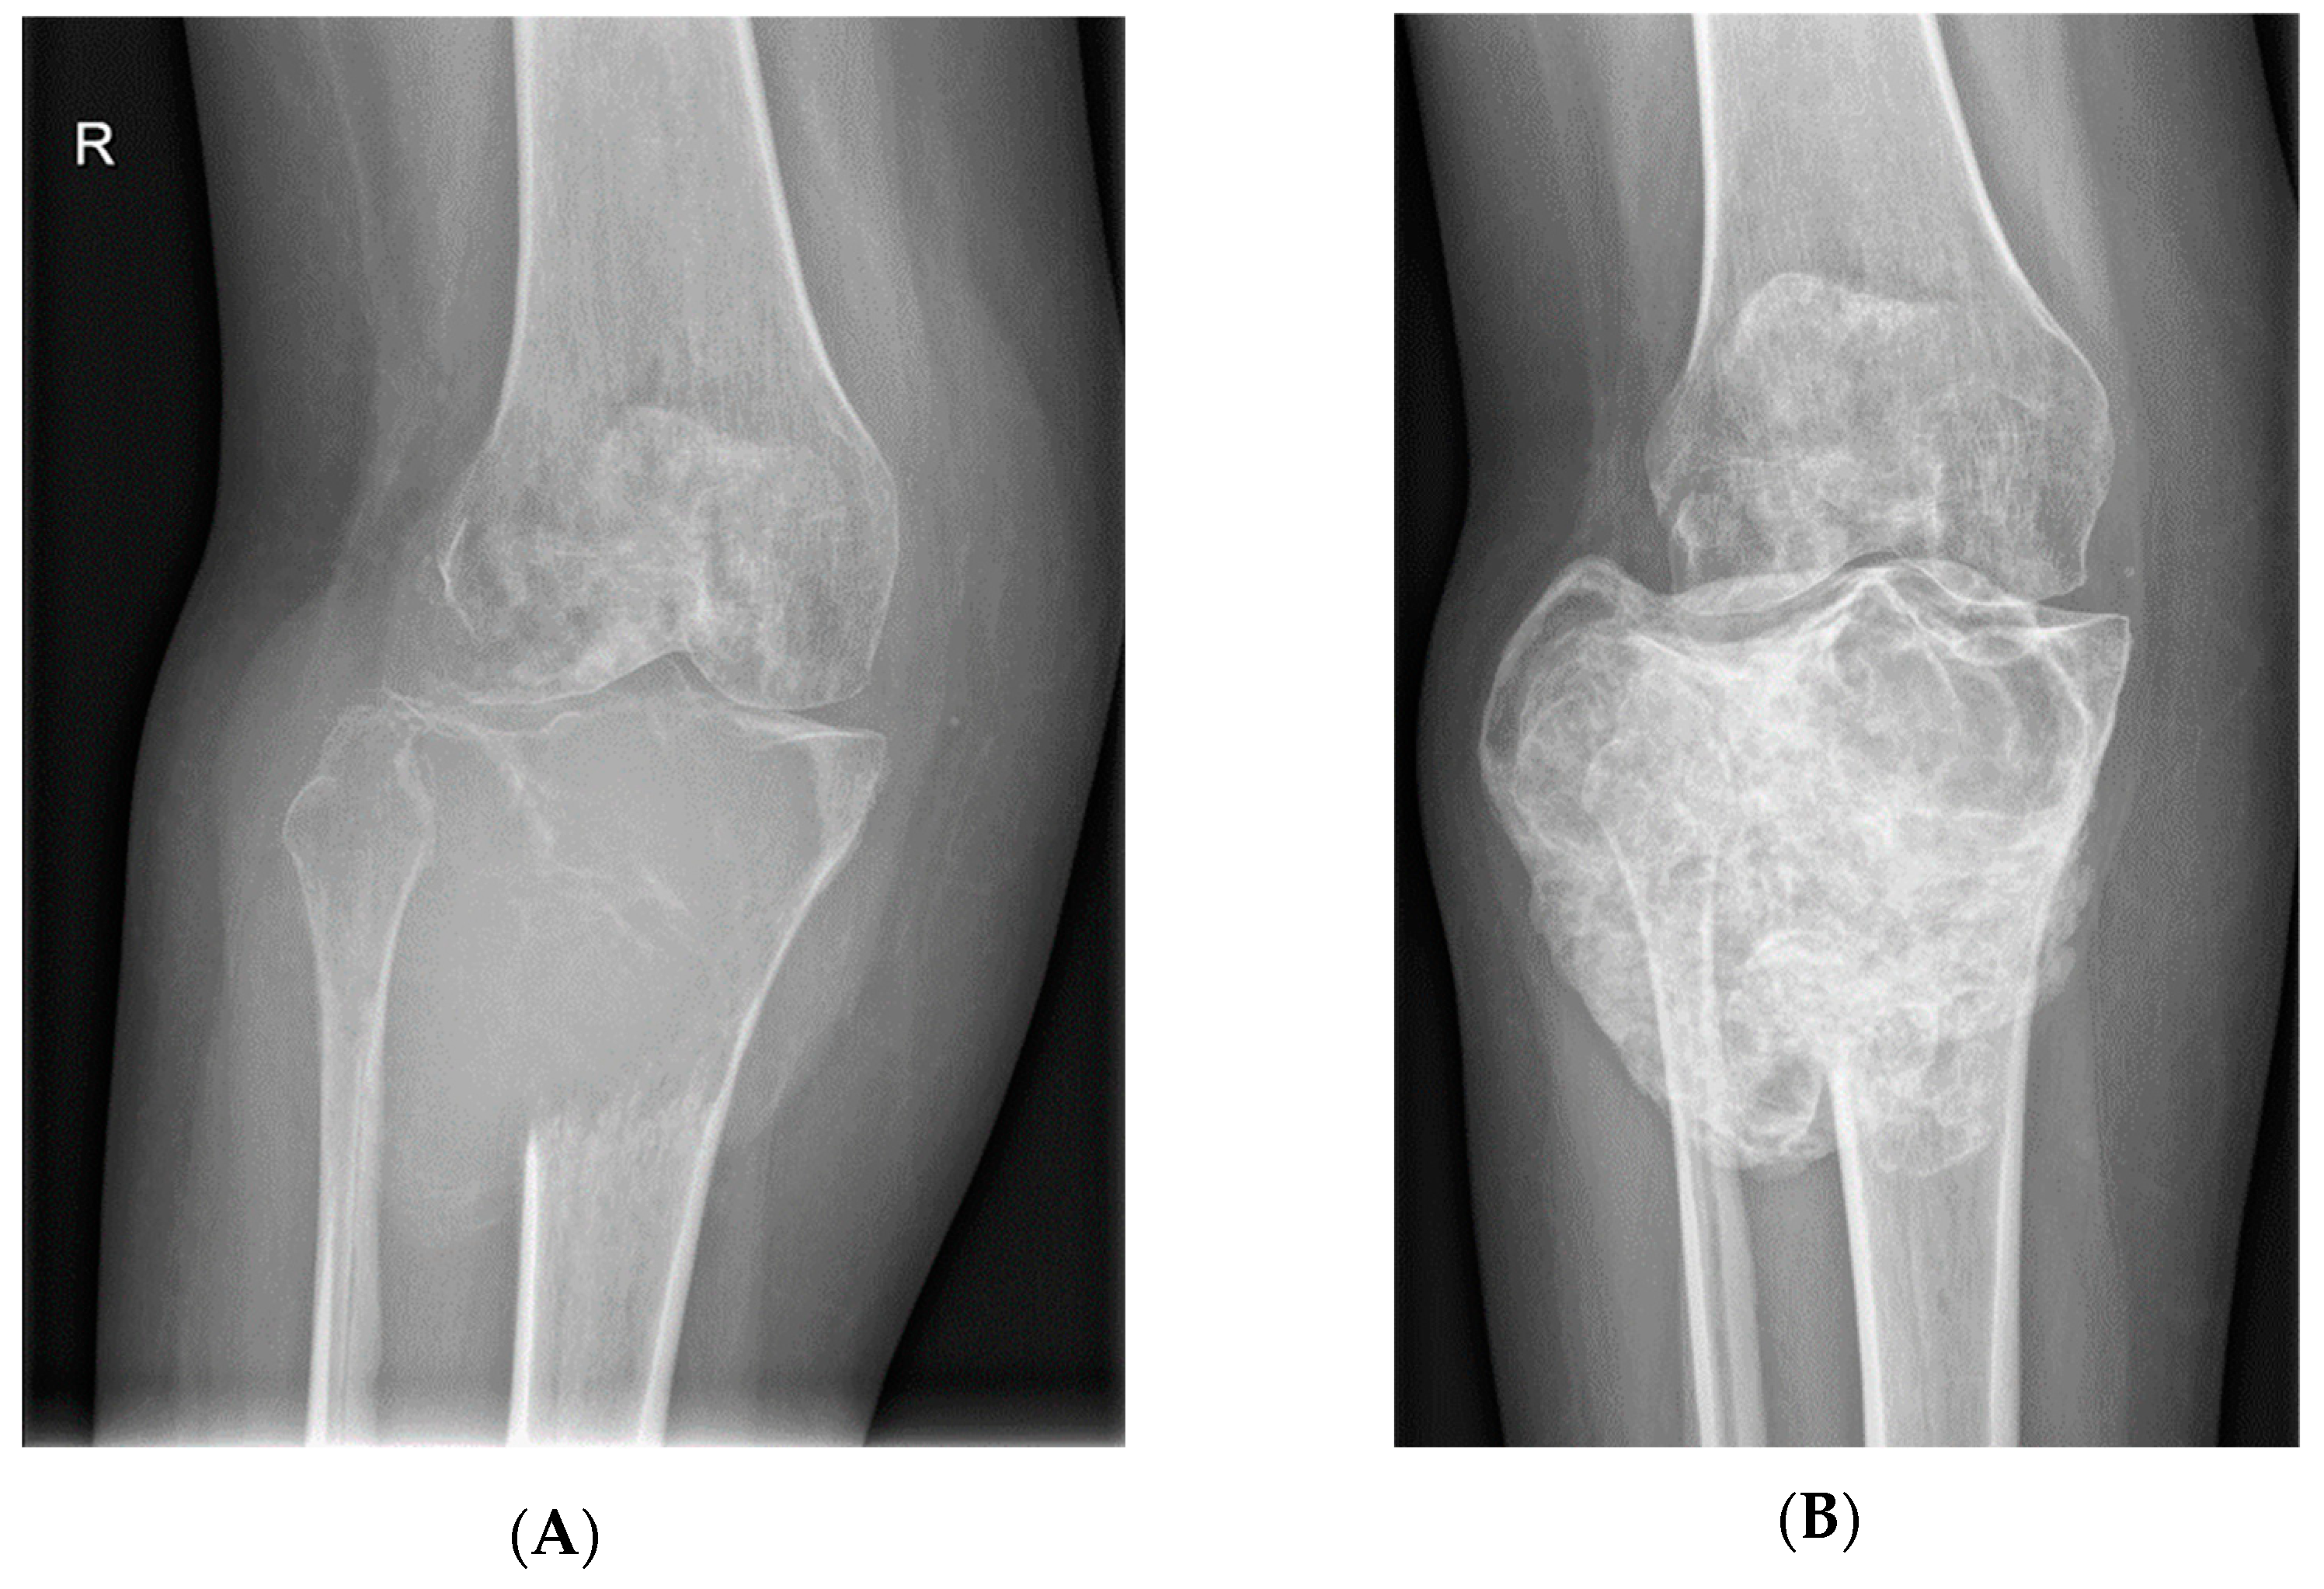

- Van Langevelde, K.; McCarthy, C.L. Radiological findings of denosumab treatment for giant cell tumours of bone. Skelet. Radiol. 2020, 49, 1345–1358. [Google Scholar] [CrossRef] [PubMed]

- Oguro, S.; Okuda, S.; Sugiura, H.; Matsumoto, S.; Sasaki, A.; Susa, M.; Morioka, H.; Jinzaki, M. Giant Cell Tumors of the Bone: Changes in Image Features after Denosumab Administration. Magn. Reson. Med. Sci. 2018, 17, 325–330. [Google Scholar] [CrossRef]

- Hakozaki, M.; Tajino, T.; Yamada, H.; Hasegawa, O.; Tasaki, K.; Watanabe, K.; Konno, S. Radiological and pathological characteristics of giant cell tumor of bone treated with denosumab. Diagn. Pathol. 2014, 9, 111. [Google Scholar] [CrossRef]

- Branstetter, D.G.; Nelson, S.D.; Manivel, J.C.; Blay, J.-Y.; Chawla, S.; Thomas, D.; Jun, S.; Jacobs, I. Denosumab Induces Tumor Reduction and Bone Formation in Patients with Giant-Cell Tumor of Bone. Clin. Cancer Res. 2012, 18, 4415–4424. [Google Scholar] [CrossRef] [PubMed]